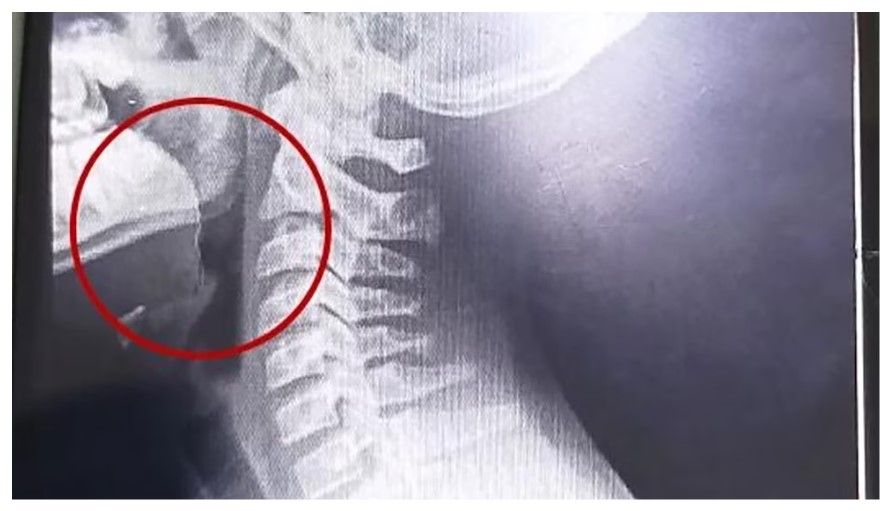

A continuación, se desarrollaron distintos estudios para descartar la presencia de infecciones o bacterias, cuyos resultados resultaron negativos. La clave para entender el cuadro apareció tras la realización de estudios por imágenes: las placas evidenciaron la presencia de un objeto extraño alojado en la vía aérea superior.

El parte médico consignó que el paciente ingresó “clínica y hemodinámicamente estable, afebril, vigil, reactivo, normohidratado y normoperfundido”, según el medio local. Luego de una interconsulta con el servicio de otorrinolaringología, se resolvió su ingreso urgente a quirófano. Allí, el equipo médico halló un alambre fino incrustado en la garganta del adolescente, situación que no había sido advertida previamente.